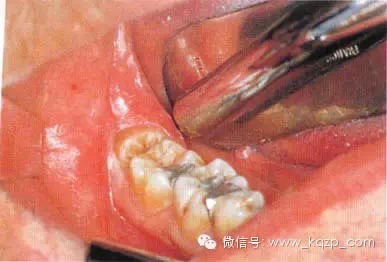

b翻瓣后,阻生牙的(牙合)面位于第二磨牙頸部及其牙槽嵴頂均清晰可見。切割牙體前先去除舌側(cè)骨板以保護軟組織

c使用紡錘形的車針( Komet - H162A.314),顯露其最大周徑至釉牙骨質(zhì)界。車針末端應進入牙槽窩內(nèi)壁